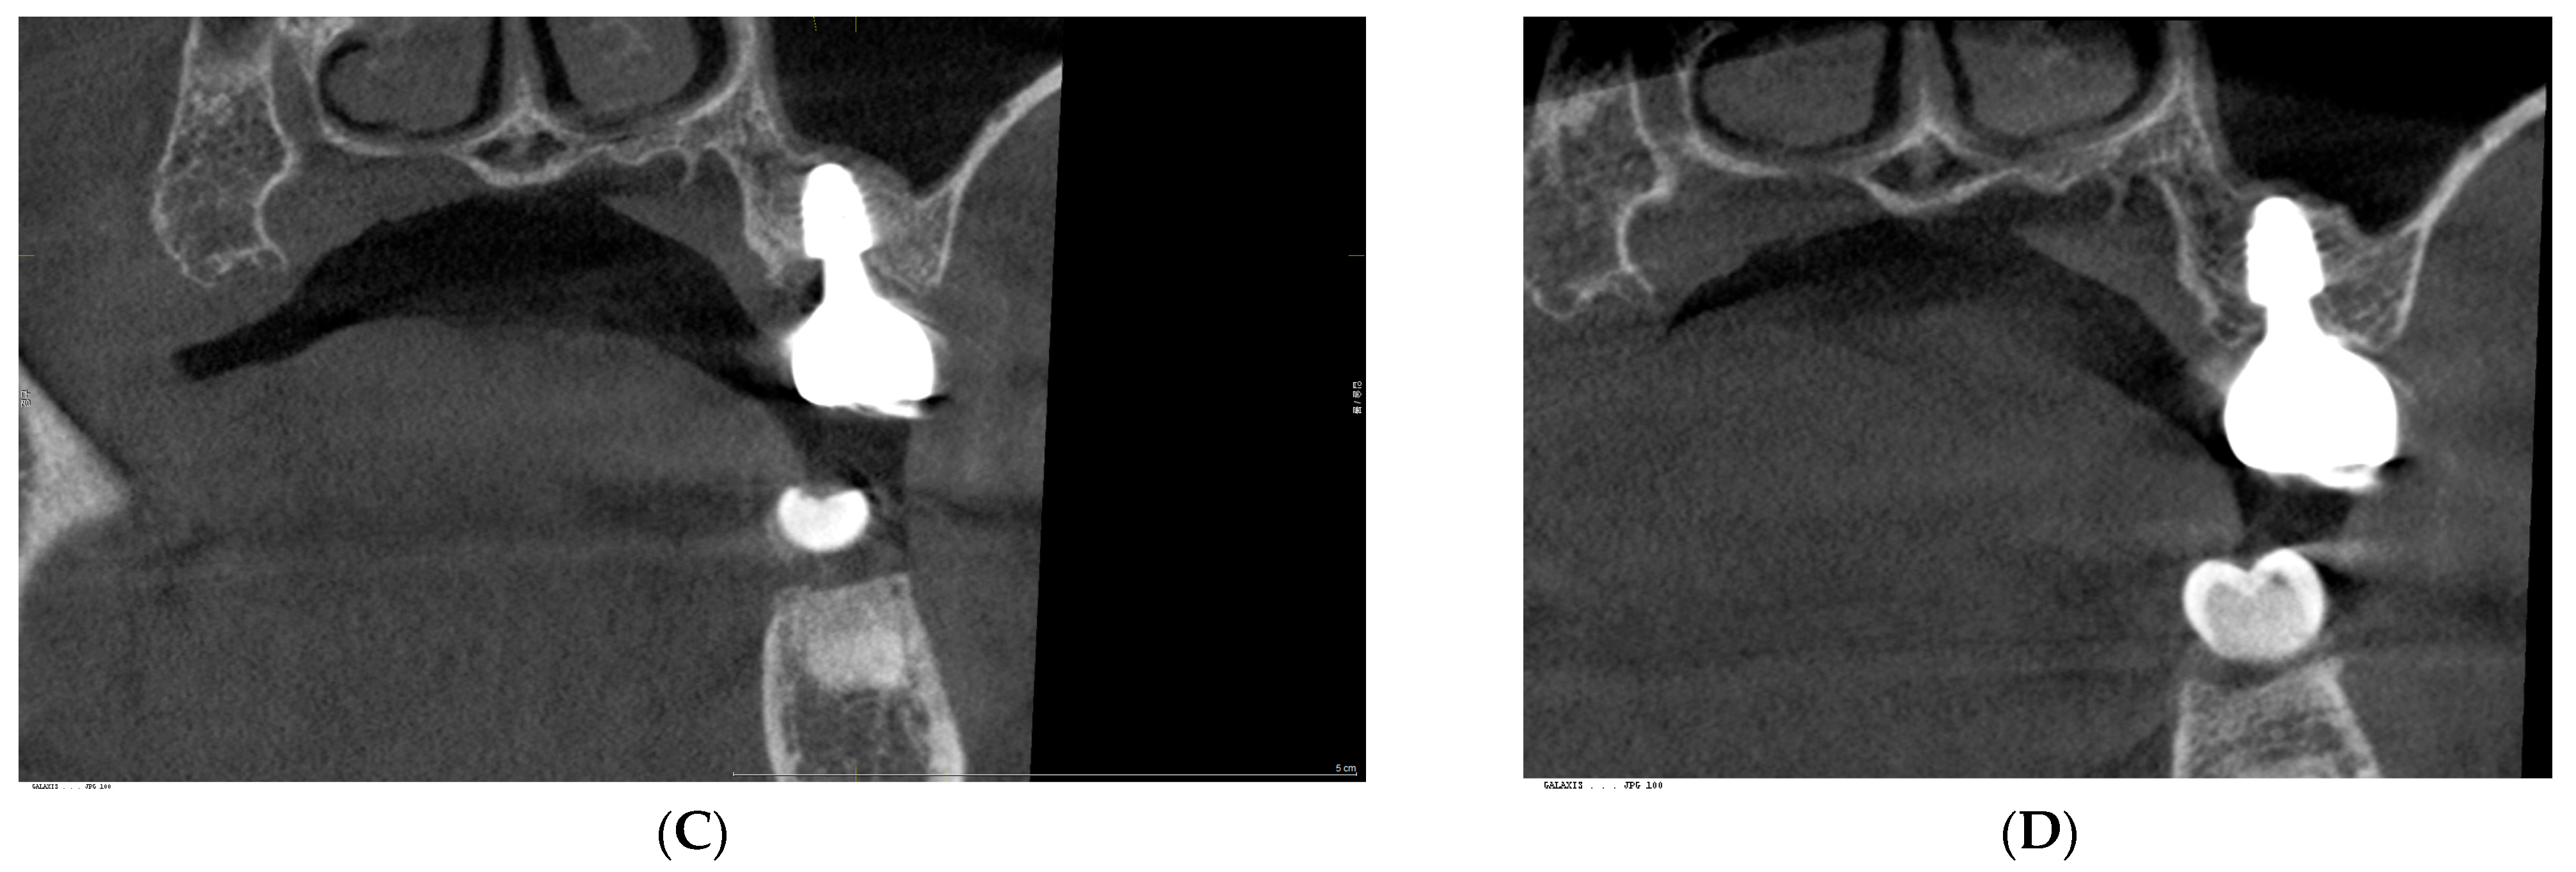

3. Radiographic and Clinical Findings

| Upper Left 1st Molar | Lower Right 1st Molar | |||

|---|---|---|---|---|

| cCRD | pCRD | cCRD | pCRD | |

| M | 1.52 | 1.91 | 0.36 | 0.91 |

| D | 1.54 | 1.87 | 0.78 | 1.66 |

| B | 1.88 | 2.04 | 0.3 | 0.3 |

| L | 0.98 | 2.05 | 0.6 | 1.41 |

| Average | 1.48 | 1.97 | 0.51 | 1.07 |